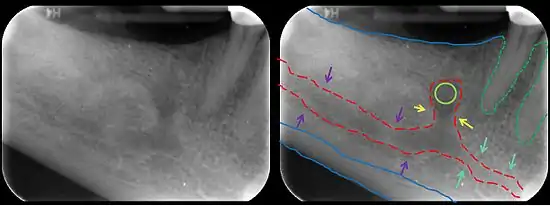

The mandibular incisive canal (indicated here by coral green arrows) continuing anteriorly (to the right) from the mandibular canal (purple arrows) after the mental foramen (light green circle)

On arriving at the incisor teeth, it turns back to communicate with the mental foramen, giving off a small canal known as the mandibular incisive canal, which run to the cavities containing the incisor teeth.[1]

It carries branches of the inferior alveolar nerve and artery.